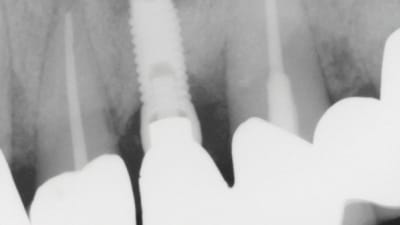

Continuing Education CE Articles Implantology Repairing an Apical Lesion Around a Dental Implant By Stephanie Tilley, DMD, Timothy Kosinski, DDS January 01, 2022